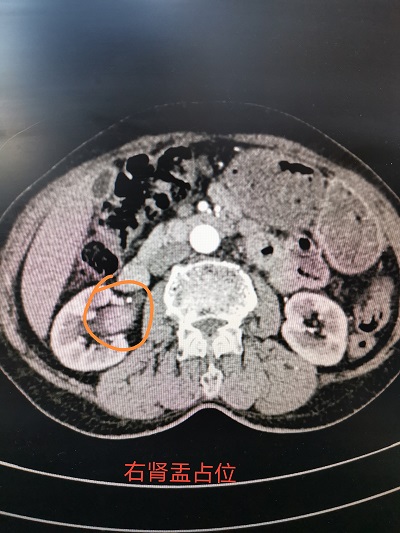

患者女性,74歲,因“間斷無痛性肉眼血尿三年”入院,經(jīng)B超、CT及膀胱鏡檢查,診斷為右腎盂腫瘤,決定行腹腔鏡下腎盂癌根治術(shù)。經(jīng)術(shù)前充分準備,在外請專家參與指導(dǎo)下,腹腔鏡下行腎盂癌根治術(shù),切除范圍包括右側(cè)病變腎臟、右側(cè)輸尿管及部分膀胱壁,手術(shù)過程順利,術(shù)中出血不多。術(shù)后標本病檢確定為腎盂尿路上皮癌,目前患者恢復(fù)良好。